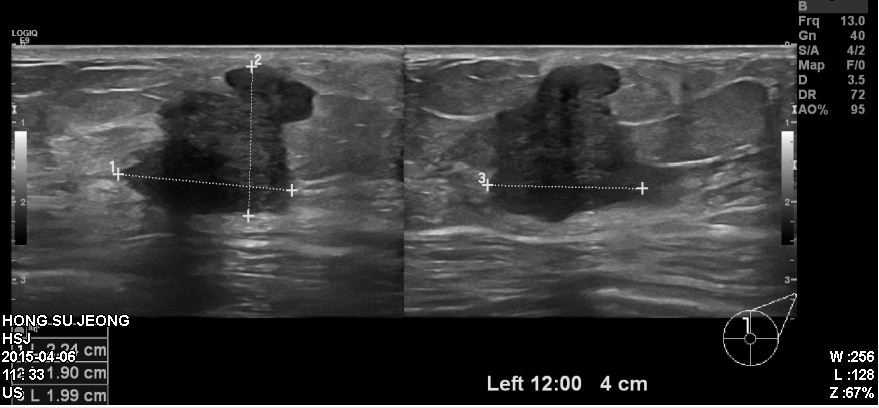

좌측유방에 만져지는 멍우리로 내원하신 60대 환자분이십니다.

본원에서 시행한 유방초음파상에 보이는

좌측유방 12시 방향에 있는 혹을 조직검사 시행하였고

침윤성유관암진단되었습니다.